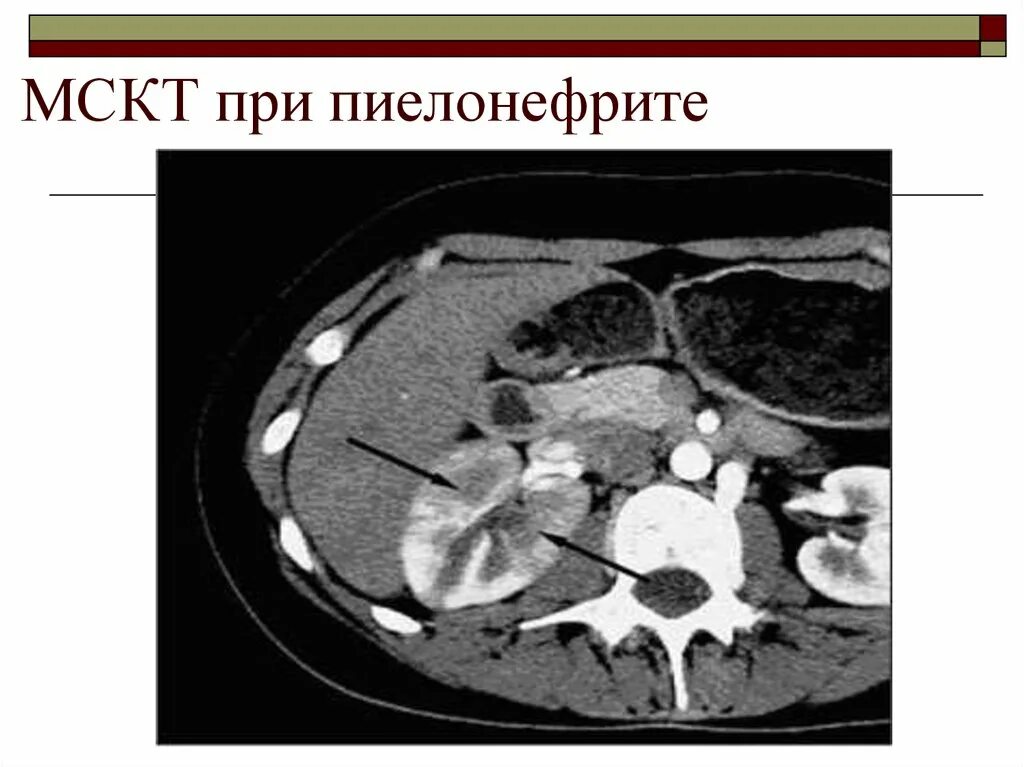

Пиелонефрит кт